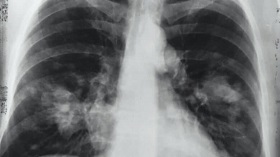

محققان دریافتند بقای سلولهای غیرطبیعی حاصل از ابتلا به کووید ۱۹ در ریه، مهمترین عامل بروز آسیبهای ریوی محسوب میشود.

به گزارش ایرنا، در نتیجه بررسیهای محققان؛ در اغلب موارد، ریه دچار آسیبهای شدید شده است و ساختار عادی ریه و بافتهای تنفسی تغییر کرده و به مواد فیبروتیک تبدیل شده است. تقریبا ۹۰ درصد این بیماران دارای دو ویژگی منحصر به کووید ۱۹، شامل وجود لختههای خون در رگهای ریه و سلولهای غیرطبیعی چندهستهای و بسیار بزرگ حاصل از امتزاج چندین سلول عادی بودند.